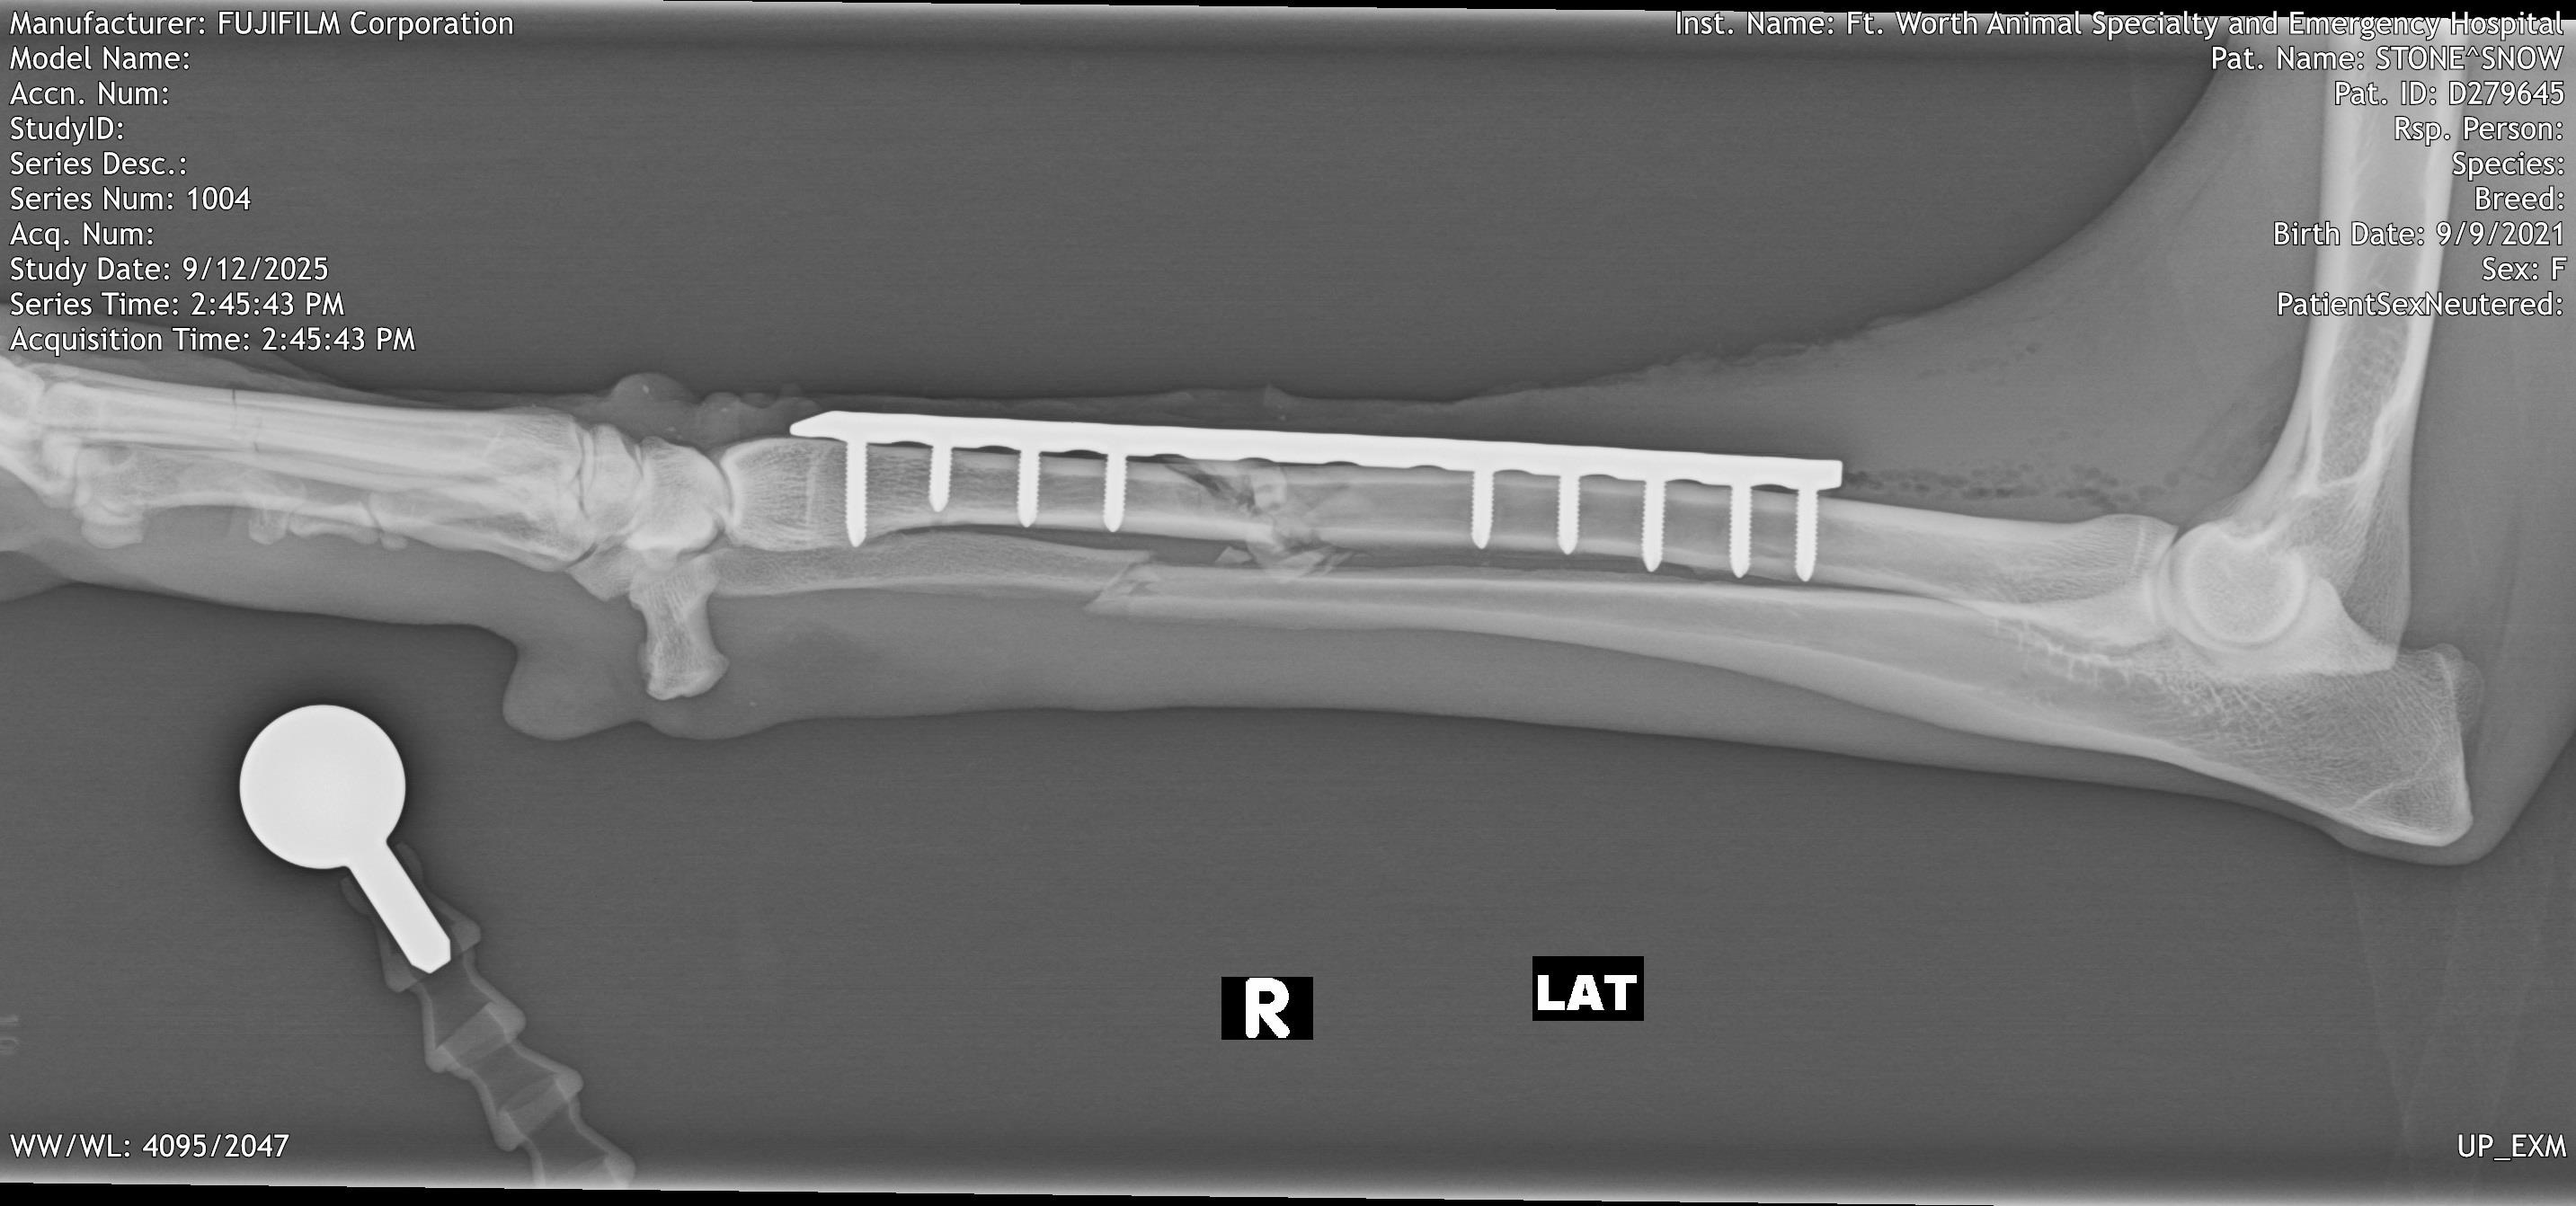

On 9/9/2025, sweet Snow the Borzoi leapt over her backyard fence and was hit by a car. She was rushed to an emergency clinic in Fort Worth, where she was diagnosed with a pneumothorax, multiple lacerations all over her body, and bilateral radial/ulnar fractures. On 9/12/25, she underwent fracture repairs at an orthopedic surgery clinic and had plates put on both legs. She was given a good prognosis.